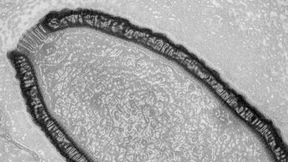

Forscher finden ein uraltes Riesenvirus in Sibirien – und erwecken es zum Leben. Die Mikroorganismen könnten möglicherweise auch heutige Menschen und Tiere gefährden.